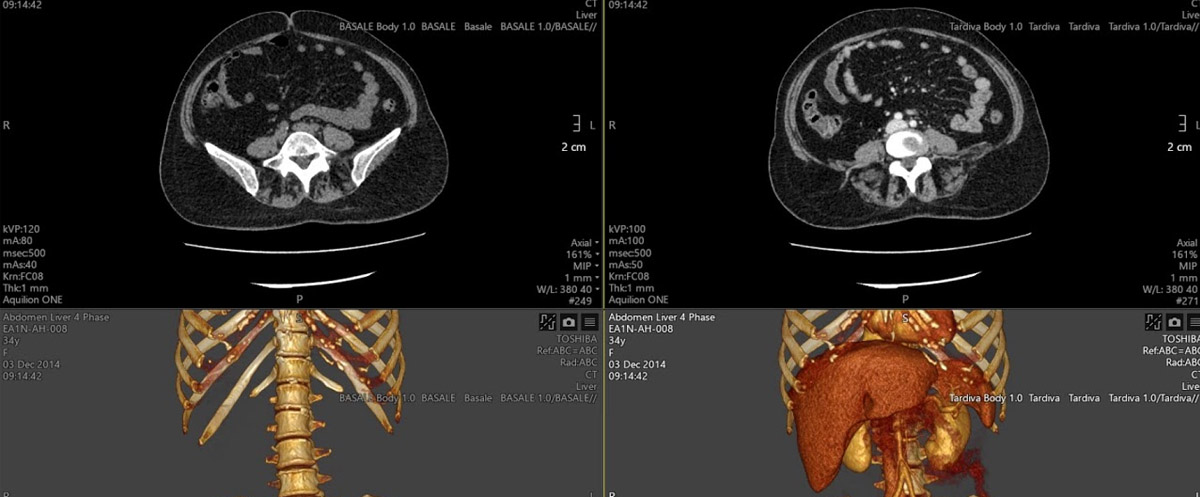

Bu yöntemde önce statik, kontrastsız çekim yapılarak tümörün yeri saptanır. Damardan kontrast madde verildikten sonra belli protokollere uyularak bir dizi ardışık dinamik görüntüler elde edilir. Bu görüntülerden ileri yazılımlar sayesinde tümör kanlanması ,kan akımı, kan hacmi, v.b. parametrelerin renkli haritaları oluşturulur.

Çeşitli kanserlerin taramaları sonucu görülen kitlelerin ayırıcı tanısı ve izleminde, beyin tümörlerinde, karaciğer kitlelerinde, tümörlerin selim ve habis ayrımında, kanser evreleme ve tedavi yanıtının saptanmasında önemli katkılar sağlayan bir yöntemdir.